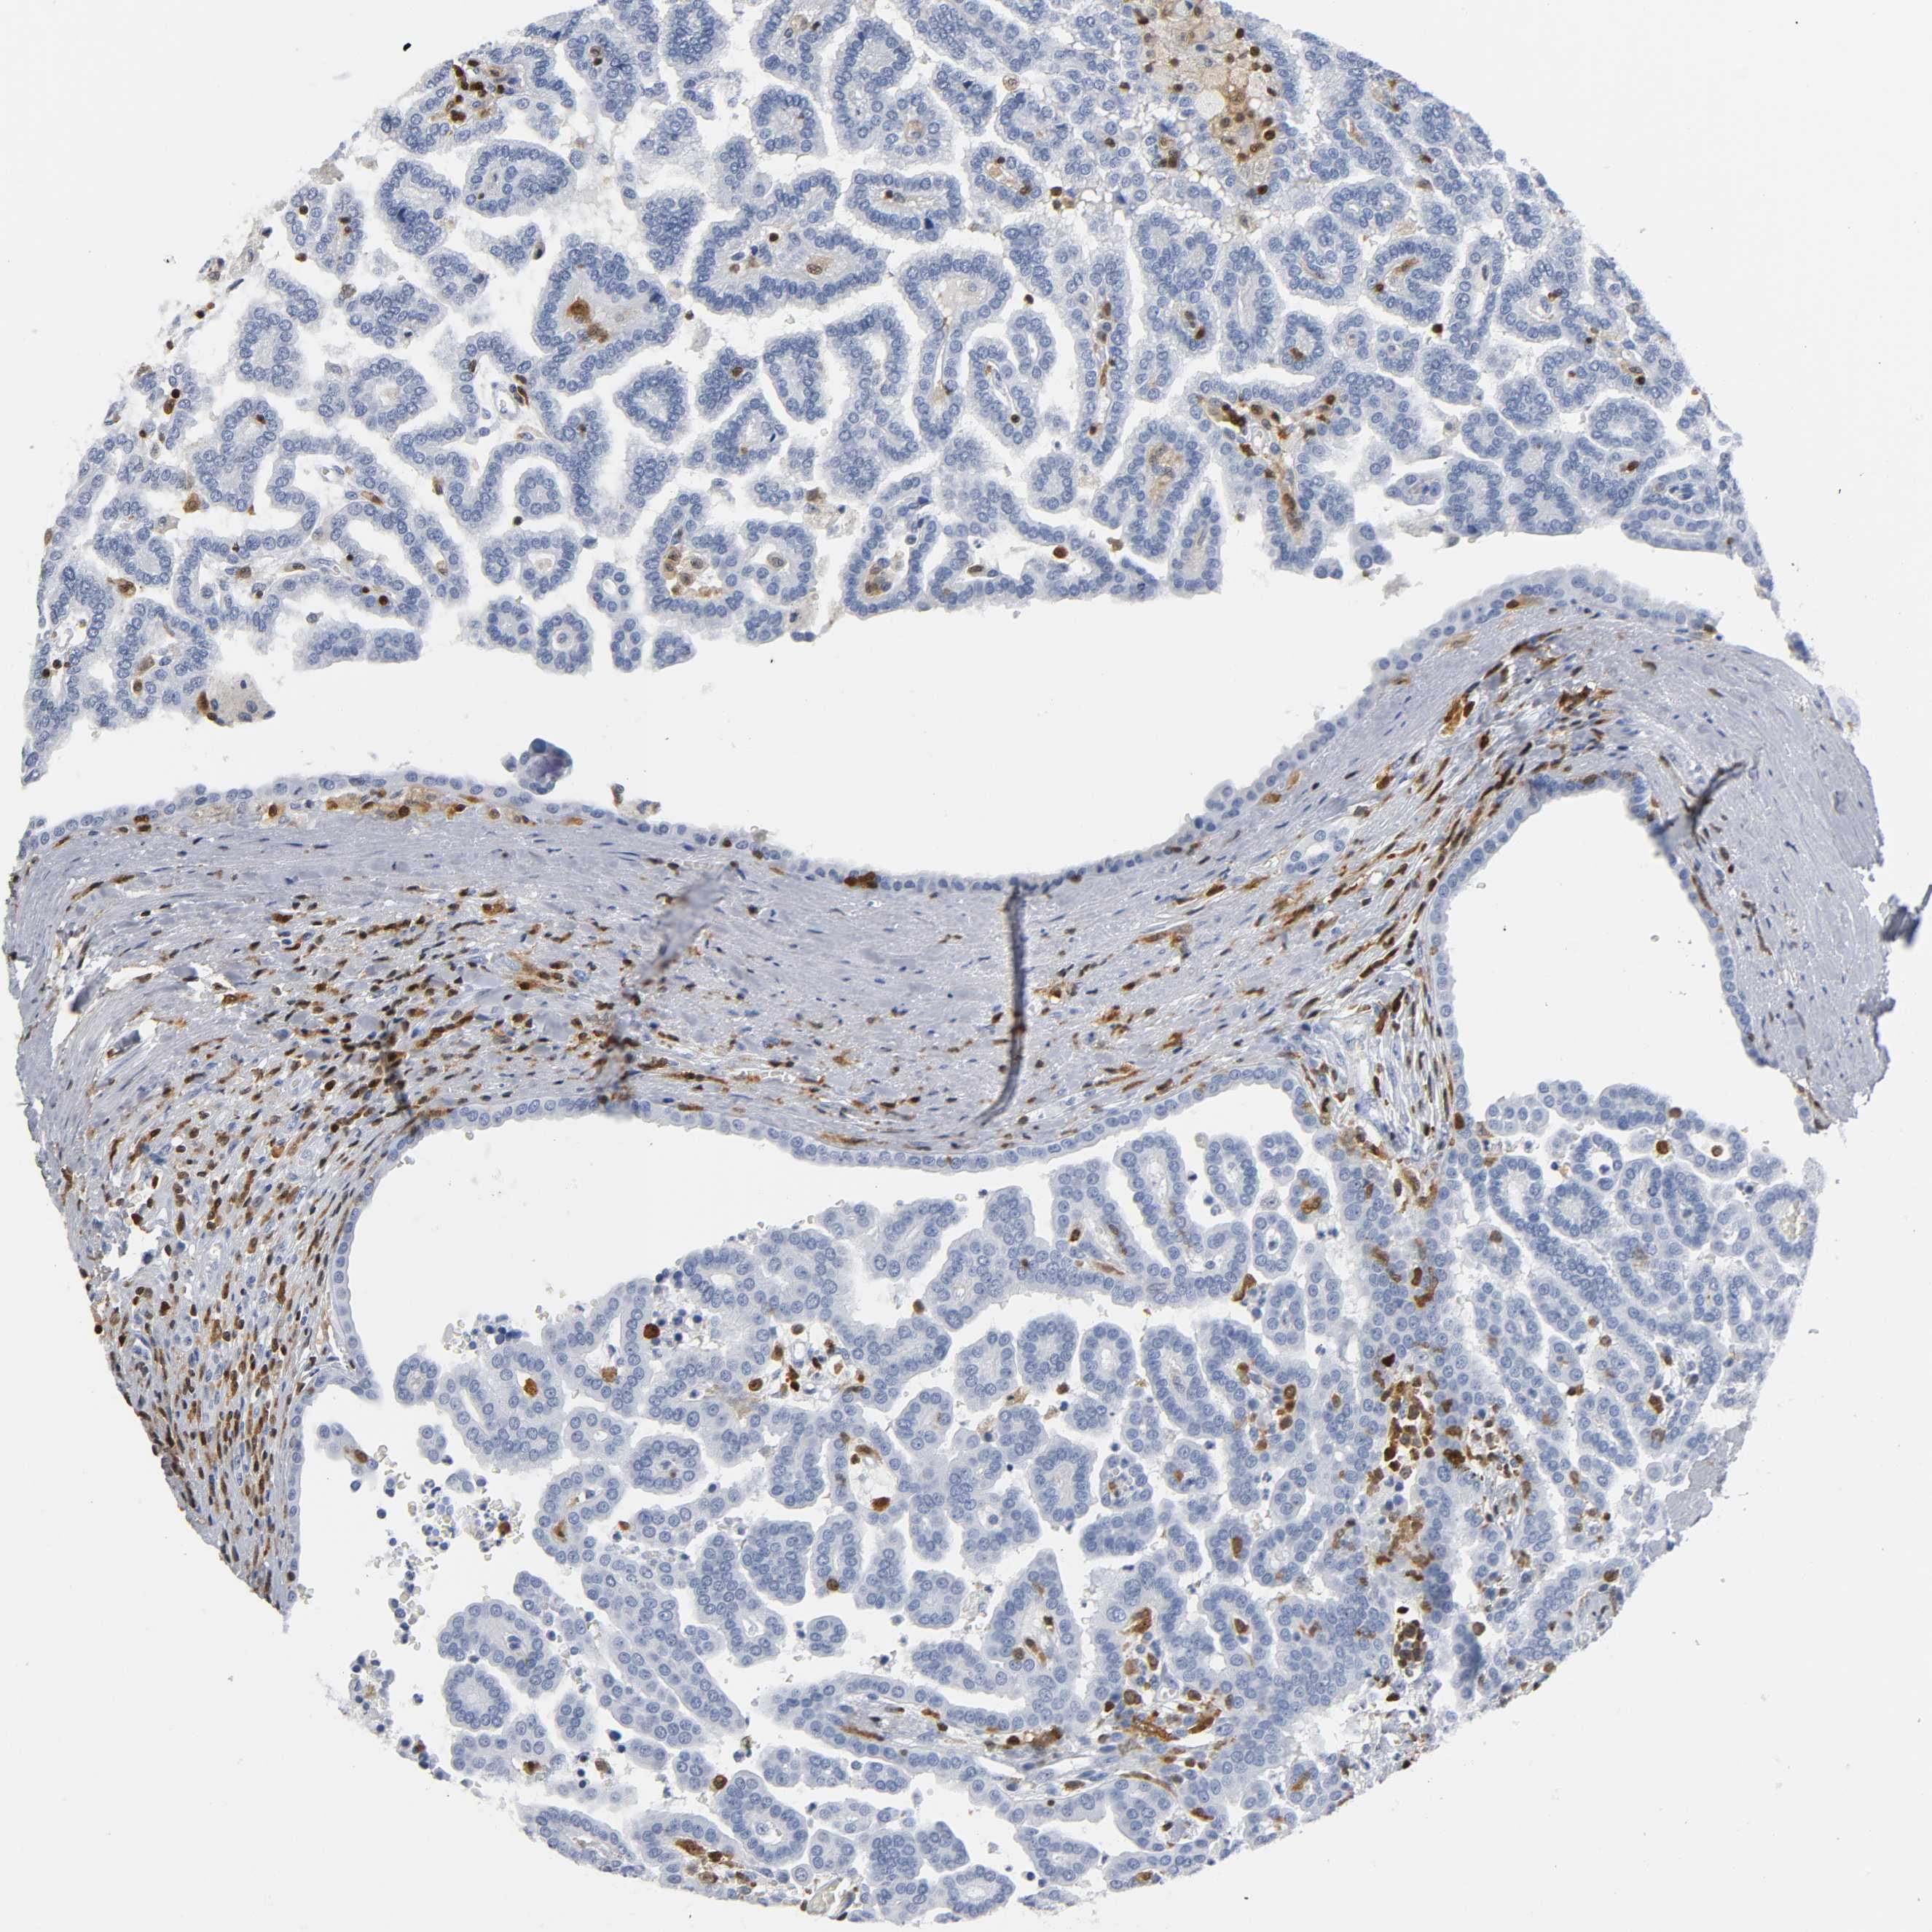

KIDNEY RENAL CLEAR CELL CARCINOMA (VALIDATION) - Interactive survival scatter ploti

The Survival Scatter plot shows the clinical status (i.e. dead or alive) for all individuals in the patient cohort, based on the same data that underlies the corresponding Kaplan-Meier plots. Patients that are alive at last time for follow-up are shown in blue and patients who have died during the study are shown in red.

The x-axis shows the expression levels (FPKM) of the investigated gene in the tumor tissue at the time of diagnosis. The y-axis shows the follow-up time after diagnosis (years). Both axes are complimented with kernel density curves demonstrating the data density over the axes. The top density plot shows the expression levels (FPKM) distribution among dead (red) and alive patients (blue). The right density plot shows the data density of the survived years of dead patients with high and low expression levels respectively, stratified using the cutoff indicated by the vertical dashed line through the Survival Scatter plot. This cutoff is automatically defined based on the FPKM cutoff that minimizes the p-score. The cutoff can be changed by dragging the vertical line or by entering a cutoff value in the square labeled "Current cut-off".

Under the Survival Scatter plot the p-score landscape (black curve; left axis) is shown together with dead median separation (red curve; right axis). Dead median separation is the difference in median mRNA expression between patients who have died with high and low expression, respectively. It is calculated as follows: median FPKM expression of dead patients with high expression - median FPKM expression of dead patients with low expression. This is intended to aid the user in visually exploring custom cutoffs and the associated p-scores and dead median separation.

Individual patient data is displayed and can be filtered by clicking on one or more of the category buttons on the top of the page. Categories describing expression level and patient information include: high, low, alive, dead, female, male and tumor stages. The scale of the x-axis can be toggled between linear and log-scale by clicking on the "x log" button. Mouse-over function shows TCGA ID, patient information and mRNA expression (FPKM) for each patient.

& Survival analysisi

Kaplan-Meier plots summarize results from analysis of correlation between mRNA expression level and patient survival. Patients were divided based on level of expression into one of the two groups "low" (under cut off) or "high" (over cut off). X-axis shows time for survival (years) and y-axis shows the probability of survival, where 1.0 corresponds to 100 percent.

DOK2 is not prognostic in Kidney Renal Clear Cell Carcinoma (validation)

Best expression cut offi

Based on the FPKM value of each gene, patients were classified into two groups and association between prognosis (survival) and gene expression (FPKM) was examined. The best expression cut-off refers the FPKM value that yields maximal difference with regard to survival between the two groups at the lowest log-rank P-value. Best expression cut-off was selected based on survival analysis .

When clicking on this number, the vertical dashed line indicating cut-off, the interactive survival plot, and the Kaplan-Meier curve will be adjusted to show results based on the best expression cut-off.

: 11.28

Median expressioni

Median expression refers to the median FPKM value calculated based on the gene expression (FPKM) data from all patients in this dataset. When clicking on this number, the vertical dashed line indicating cut-off, the interactive survival plot, and the Kaplan-Meier curve will be adjusted to show results based on the median expression.

: N/A

Median follow up timei

Median follow up time refers to the median time (years) after diagnosis with this type of cancer, based on clinical data from all patients in this dataset.

P scorei

Log-rank P value for Kaplan-Meier plot showing results from analysis of correlation between mRNA expression level and patient survival.

N/A

5-year survival highi

5-year survival for patients with higher expression than the expression cutoff.

For melanoma and glioma, 3-year survival is shown.

5-year survival lowi

5-year survival for patients with lower expression than the expression cutoff.

TCGA RNA samplesi

RNA-seq data is reported as average FPKM (number Fragments Per Kilobase of exon per Million reads), generated by the The Cancer Genome Atlas (TCGA) .

Normal distribution across the dataset is visualized with box plots, shown as median and 25th and 75th percentiles. Points are displayed as outliers if they are above or below 1.5 times the interquartile range. FPKM values of the individual samples are presented next to the box plot.

Average pTPM 11.3

Number of samples 100